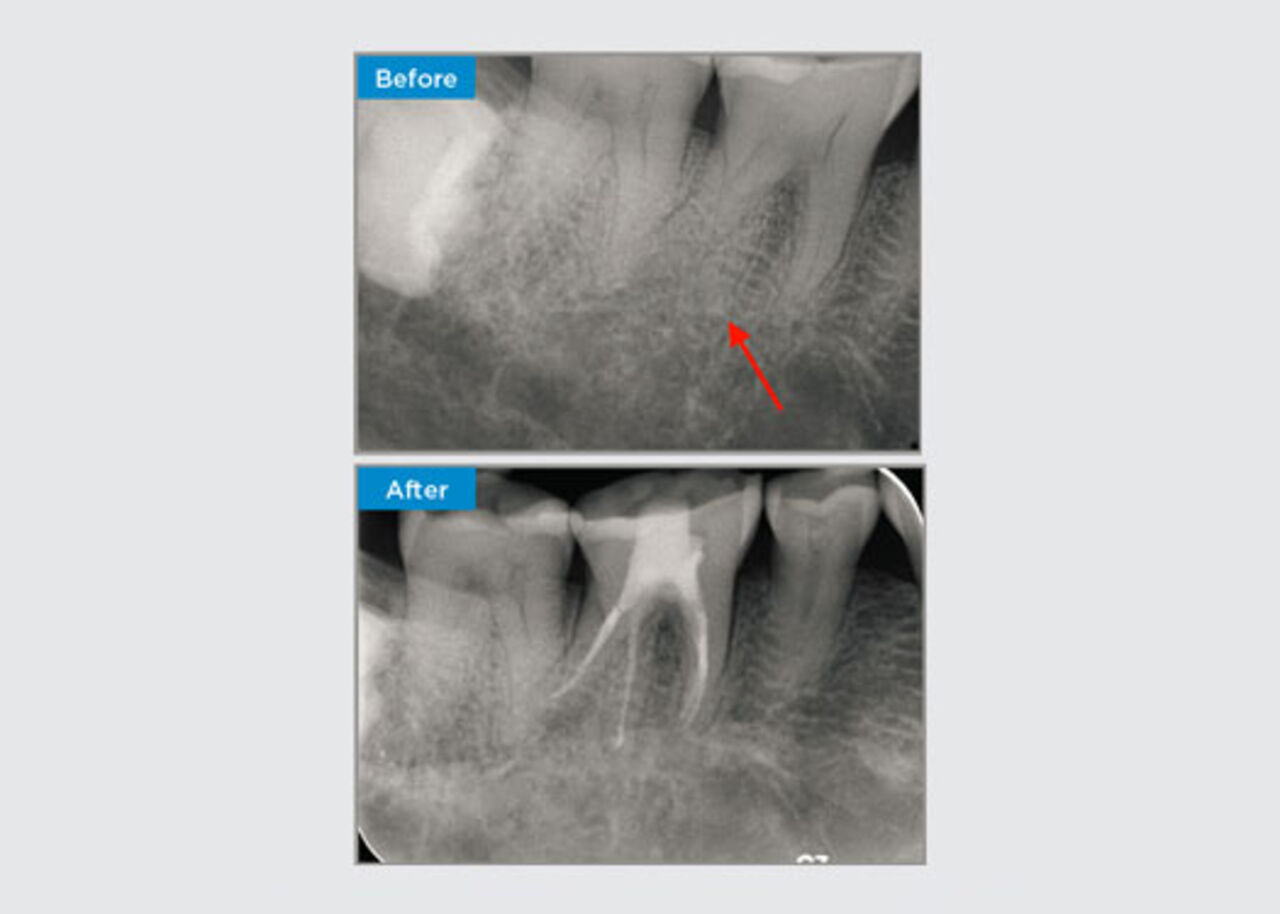

Clinical Cases

Clinicians far and wide, throughout Australia and New Zealand kindly share relevant, interesting and sometimes challenging patient presentations, along with their selection of materials and methods to optimise their patients' outcomes.